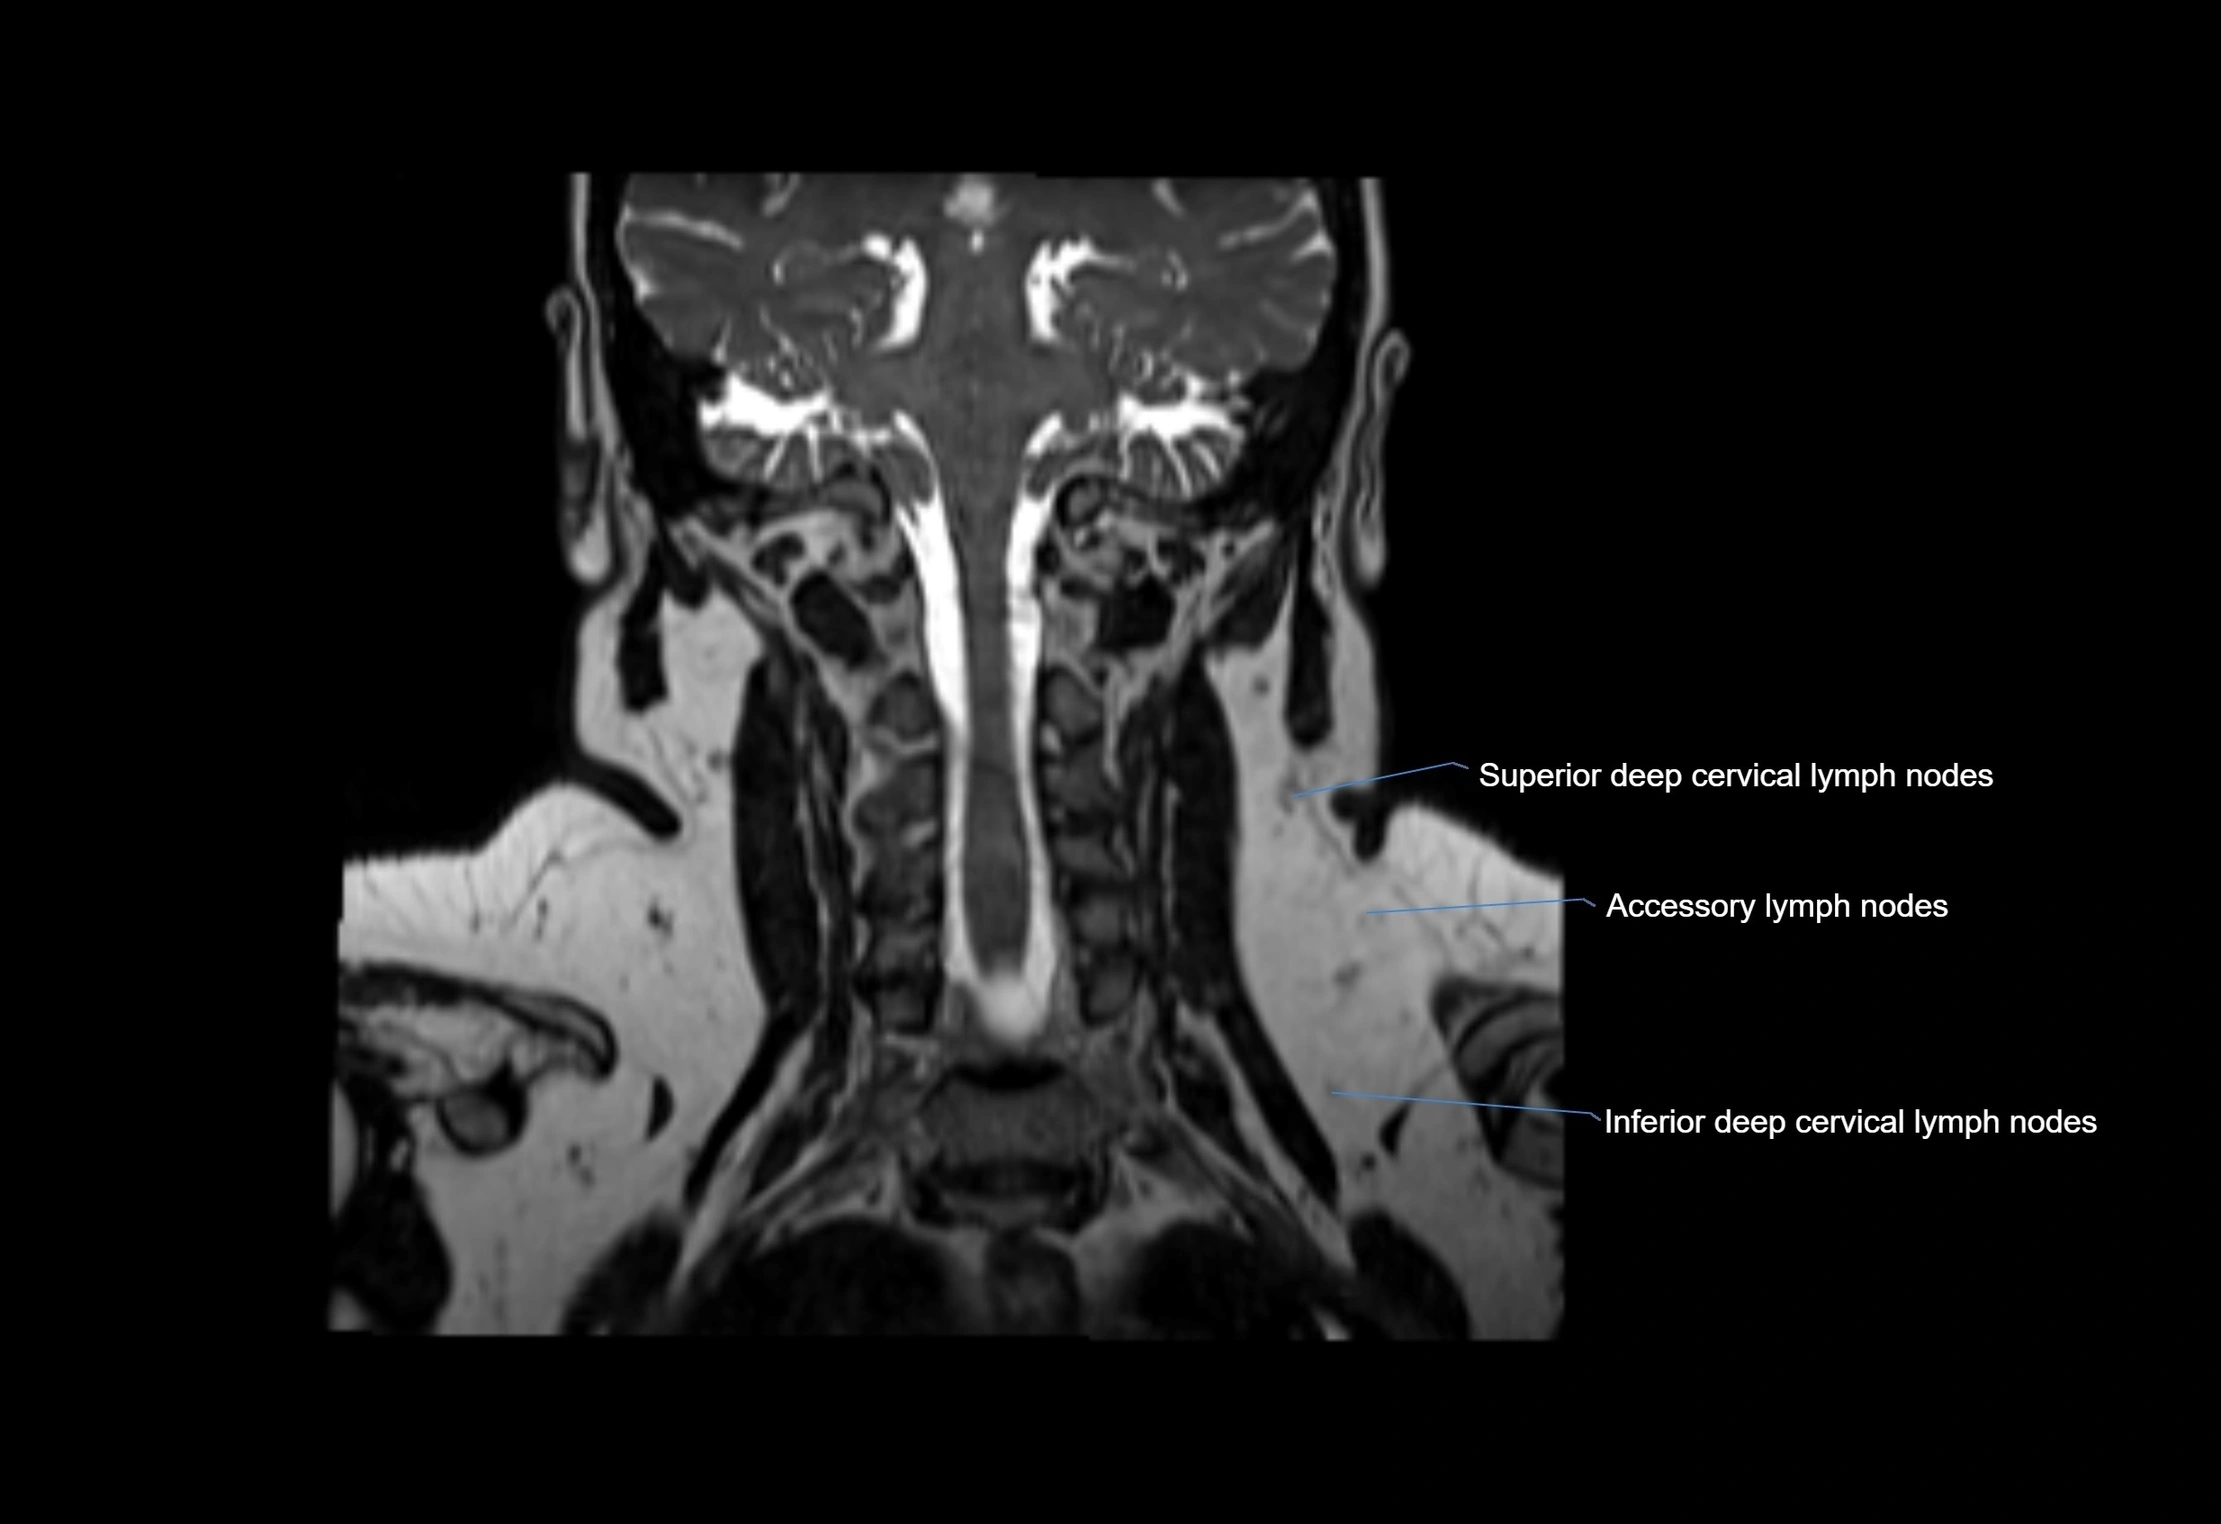

Accessory lymph nodes

Accessory lymph nodes are small, secondary lymph nodes located along the main facial and cervical lymphatic chains, often adjacent to primary lymph nodes, such as preauricular, submandibular, or occipital nodes. They are typically less than 5 mm in diameter, embedded within subcutaneous fat or connective tissue, and may be variable in number and location. These nodes provide additional filtration and immune surveillance for lymph collected from the face, scalp, and neck regions. Accessory lymph nodes are usually non-palpable in healthy individuals but may enlarge in response to infection, inflammation, or metastasis, making them clinically significant.

Location

• Found along primary lymph node chains, including preauricular, submandibular, parotid, and occipital regions

• Embedded in subcutaneous fat or superficial fascia, often lateral or posterior to primary nodes

• Variable in number; may occur unilaterally or bilaterally, depending on individual anatomy

MRI images

image